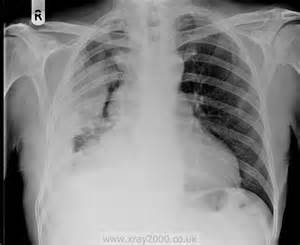

Rentgen – ilkin müayinədir, pnevmotoraksı və bəzən də plevrada mayeni dəqiqləşdirən müayinədir.

Plevrada mayeni rentgen göstərə bilər. Qabırğa-diafraqma cibinin düzləşməsi, plevrada homogen kölgəlik, Damuaze xətti mayenin rentgenoloji əlamətləridir. Qabırğa-diafraqma xəttinin düzləşməsi plevrada ən azı 250 ml mayenin olduğunu göstərir. Lakin, mayeni görmək üçün ən həssas müayinə USM-dir.